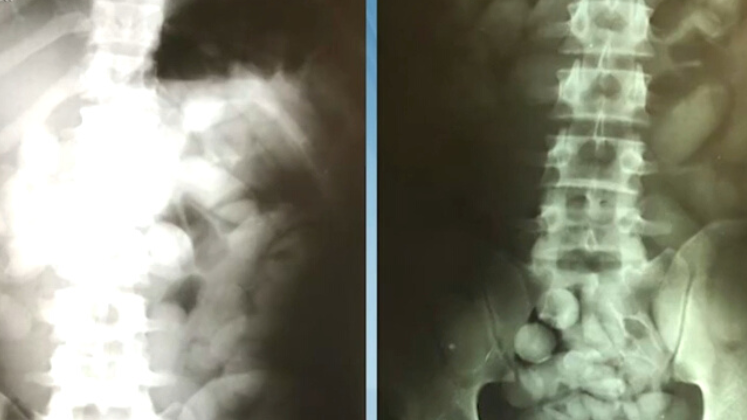

Cada um estaria levando meio quilo de cocaína no estômago, embalada em cápsulas. A informação é de um site do Brasil que divulga notícias do Líbano – Foto: Reprodução/Record TV/ND